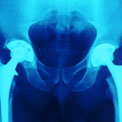

Glenn, 54, a married father of one teenage daughter living in New York State, was a longtime fitness buff who lived with unbearable pain in both of his hips. Knowing that he’d have to replace them, he made the bold decision to have double hip replacement surgery, a choice that made his recovery significantly more challenging. He spoke with Health.com just a month after the operation.